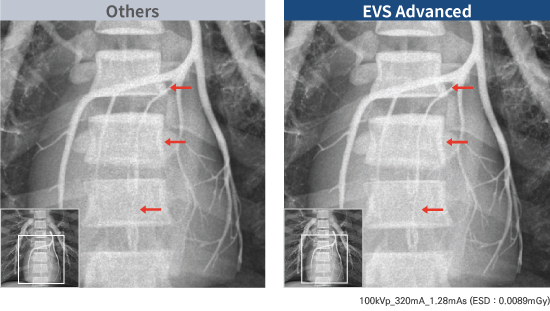

Actualizaciones tecnológicas en EVS

Advanced Series

La serie EVS Advanced proporciona una excelente experiencia de imagen en reducción de dosis y claridad diagnóstica.

FOCUS (estructura mejorada CsI óptica fluorescente) tiene una señal óptica más enfocada en comparación con CsI convencional. Como resultado, la tecnología FOCUS logra un ruido ultrabajo.

2 veces mayor DQE en dosis bajas

EXPRIMER Advanced Series proporciona una alta calidad de imagen con un 50 % menos de dosis que CR y un 25 % o más de dosis reducida en comparación con DR.

Experimente la reducción de la dosis del paciente

La dosis reducida para el paciente se logra a través del potente rendimiento de dosis baja de EXPRIMER Advanced Series.